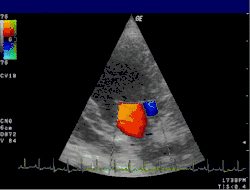

Technika kolorowej ultrasonografii dopplerowskiej (kolorowy doppler) polega na barwnym obrazowaniu przepływu krwi w naczyniach. Umożliwia to precyzyjną lokalizację nawet małych naczyń zaopatrujących poszczególne struktury. Uwidaczniane zmiany nasycenia kolorem odpowiadają różnym szybkościom przepływu krwi, pokazując tym samym naczynia o nieprawidłowej budowie ściany. Jest to szczególnie istotne przy powikłaniach ciąży, w przypadku szybko rosnących guzów, w tym nowotworów złośliwych, oraz przy wczesnym rozpoznawaniu zmian w miąższu wątroby[3].